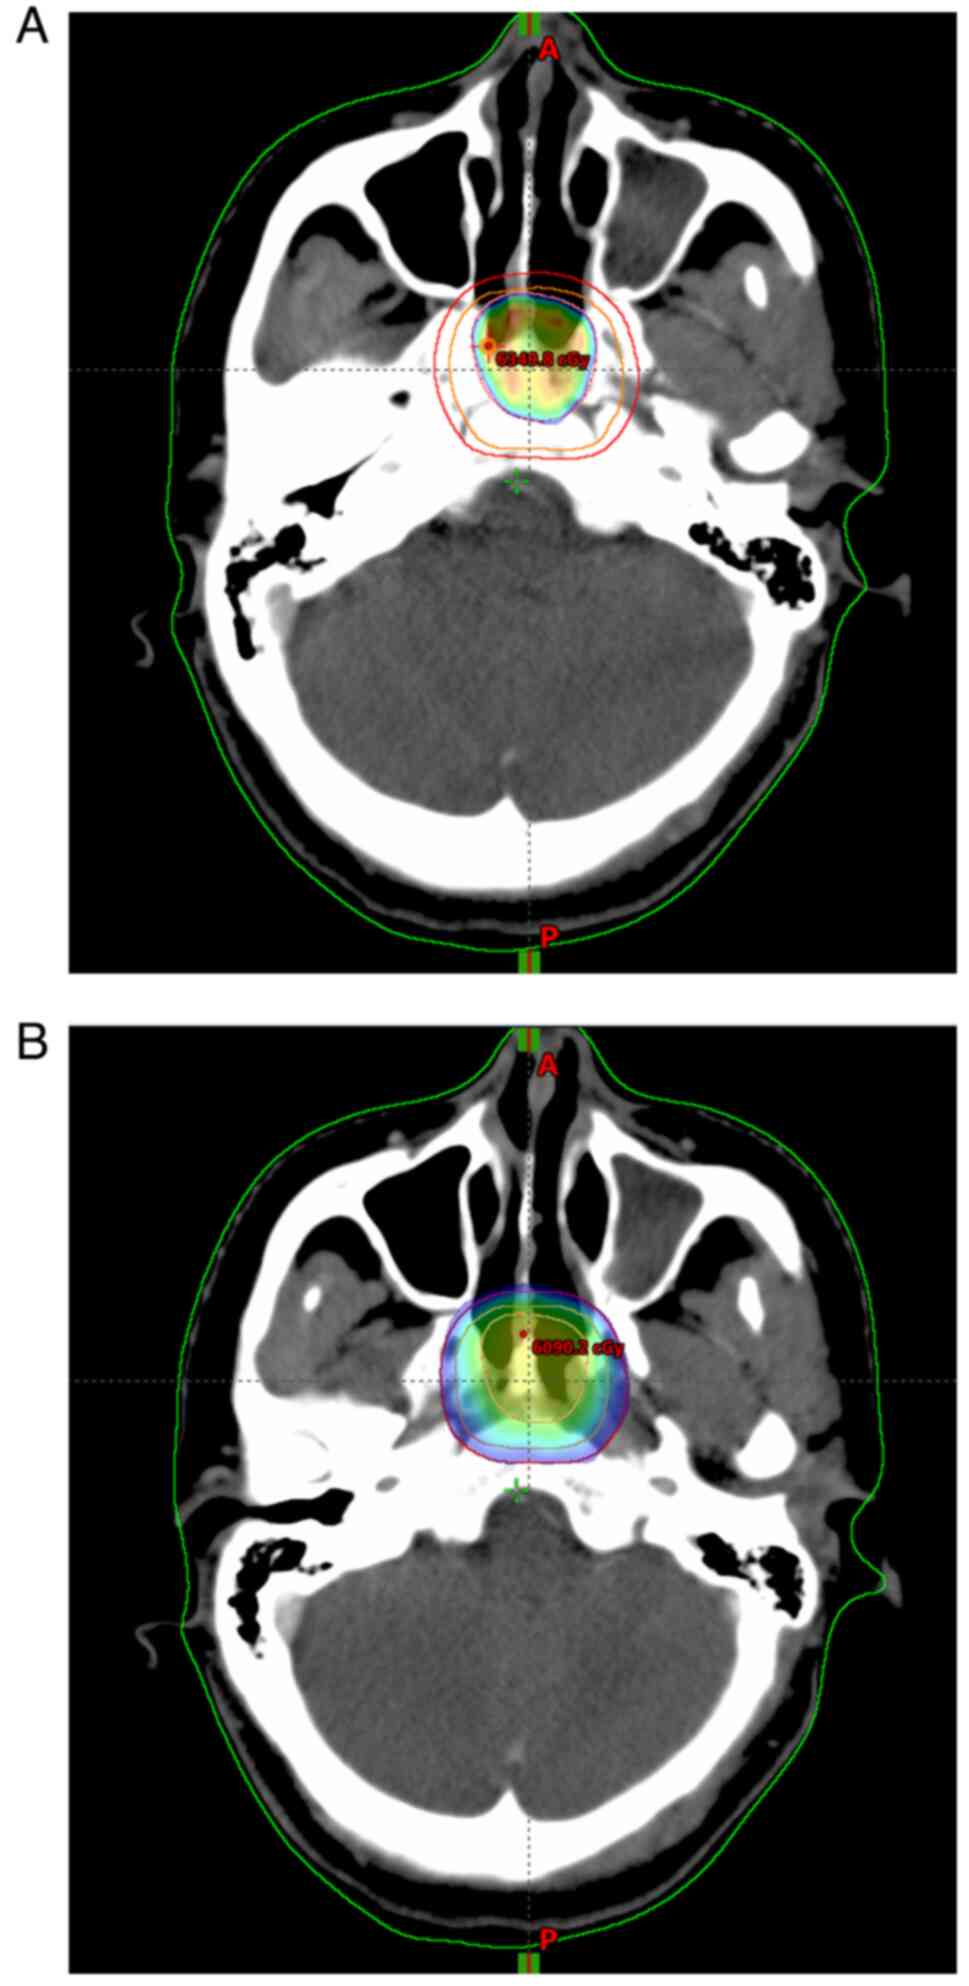

Figure 4.

Dose distribution images of adjuvant radiotherapy. (A) Radiation therapy to a dose of 60.0 Gy (planning gross tumor volume). (B) Radiation therapy to a dose of 50.0 Gy (planning clinical target volume).